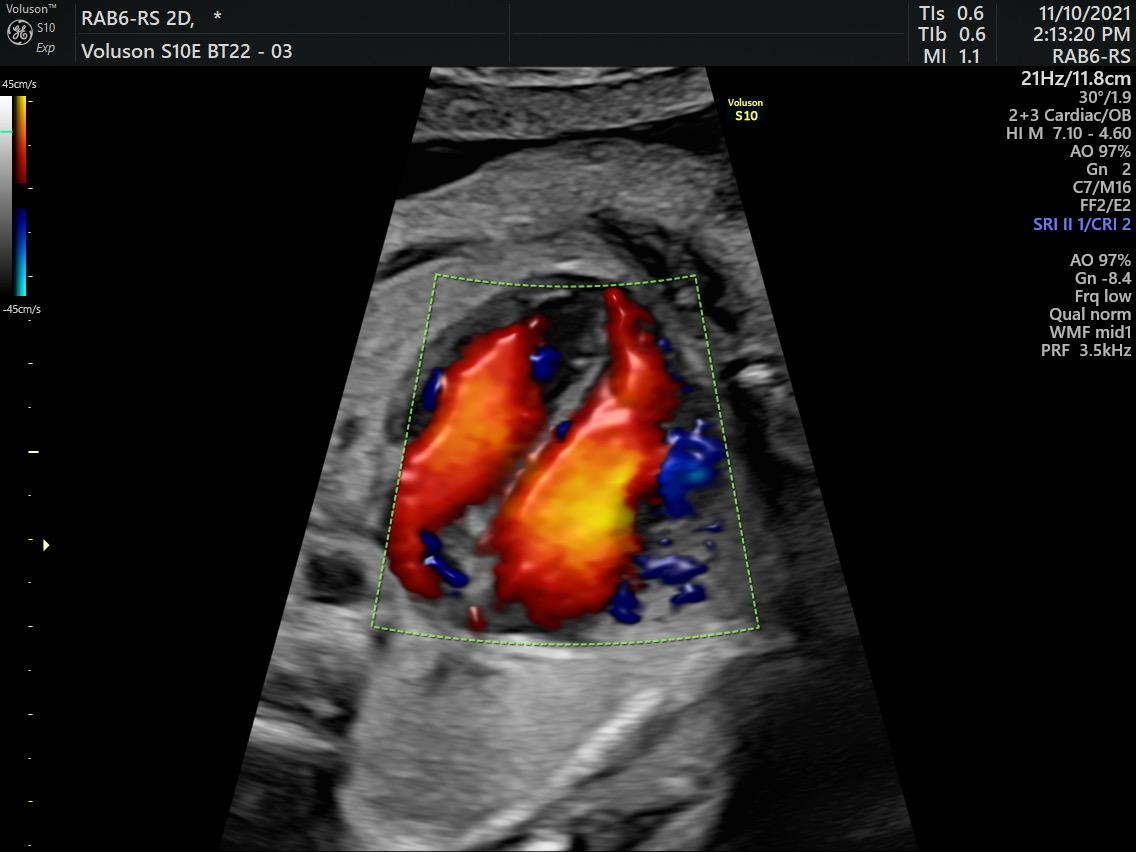

Fetal Medicine

Ultra Sound

Gallery

Images

Photos